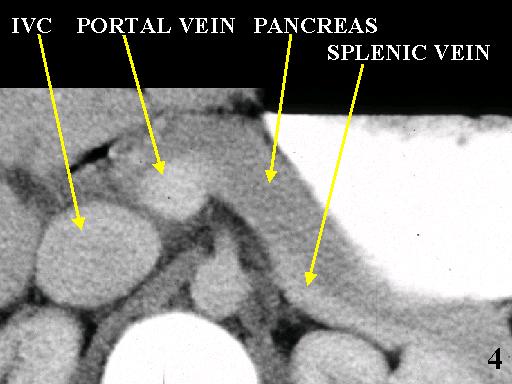

MS 190 CT 15